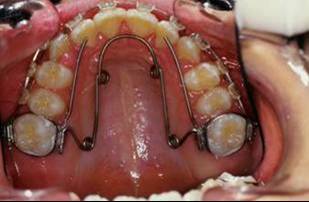

la suite de documents, comme vous allez le voir le premier moyen est un qh, mais quelle sera la suite?

1- RDV 1: QH

2- RDV 2 : Commencer avec ecran buccal + exercice de respiration

3- Quant elle est capable de garder oral screen toute la nuit je considere que la batail est gagnee

4- Collage de l'arcade sup, presque 6 mois apres et voici le photo apres seance de college

J'ai oublie de signaler que depuis RDV 4 une reeducation linguale, au cabinet faite par moi-meme, a commence.